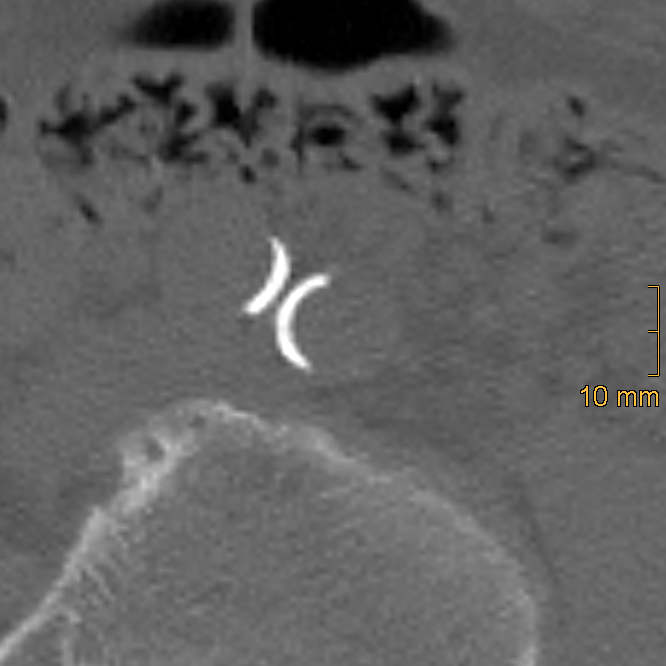

2.2. Assessment of Vascular Calcification

2.2.1. Abdominal Aortic Calcification